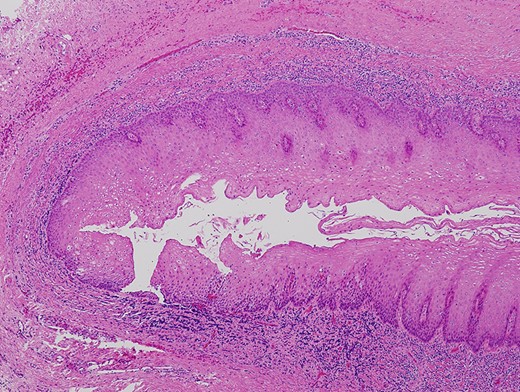

A 66-year-old man was referred to our institution in January 2018 for the diagnosis and treatment of a right buccal lesion. The lesion was first noticed approximately 1 month previously during an examination by his family dentist. The patient’s medical and family histories were unremarkable. He had no history of trauma to the face. Physical examination revealed bruising on the skin of his right cheek (Fig. 1). In the oral cavity, a mucosal outpouching (5-mm diameter, 10-mm depth) was observed in his right cheek. Food debris was seen in the outpouching (Fig. 2). The adjacent overlying oral mucosa was normal in appearance. The clinical diagnosis was a diverticulum-like lesion of the buccal mucosa. Excision of the outpouching was performed through an intraoral incision to stop food impaction (Fig. 3). It was easily separated from the surrounding soft tissues and completely excised (Fig. 4). The bottom of the outpouching was over the buccinator muscle on the lateral side. The buccinator muscle layer and oral mucosal layer were sutured separately. Histopathological examination revealed that the excised lesion was a true diverticular structure composed of a keratinising, squamous epithelial lining with a surrounding fibrous connective tissue wall, with inflammatory cell infiltration and haemorrhage (Fig. 5). In contrast to the normal buccal mucous epithelium, the diverticular epithelium had a thick stratum spinosum appearance with formation of anastomosed rete ridges (Fig. 6). The surface of the parakeratinised epithelium was corrugated. The histopathological diagnosis was a diverticulum of buccal region. The postoperative course was uneventful.

Histopathologic findings of the lesion revealed a true diverticulum composed of an inner layer of squamous epithelium and an outer layer of fibrous connective tissue (haematoxylin–eosin stain, ×5).

Diverticular epithelium showing a thick stratum spinosum appearance with formation of anastomosed short and broad rete ridges and a corrugated epithelial surface (haematoxylin–eosin stain, ×40).

Oral diverticula are exclusively located on the buccal mucosa of older adults. Except for one large diverticulum reported by Bailey [3], oral diverticula are relatively small (≤15 mm in both diameter and depth). Clinical symptoms of an oral diverticulum include swelling [3], halitosis [5, 7], bleeding [3], and food impaction [7]. Three reported cases [4–6] were followed up with conservative treatment, and surgical excision was performed in another three cases [3, 7, 8]. The aim of the surgery was to stop food impaction into the diverticulum [7, 8]. In the present case, surgical resection was selected for the same reason. Histopathologically, the diverticular epithelium showed a corrugated surface layer and rete ridge formation. Such histologic architecture may suggest that the diverticular mucosa is able to expand. Inflammatory cell infiltration and haemorrhage were observed under the epithelium. These findings have not been documented in the English-language literature to date. However, bleeding has been reported as a clinical symptom of oral diverticulum [3]. In the present case, bruising on the skin of the right cheek and histopathological findings of chronic inflammation suggested the occurrence of subepithelial bleeding under the outpouching.